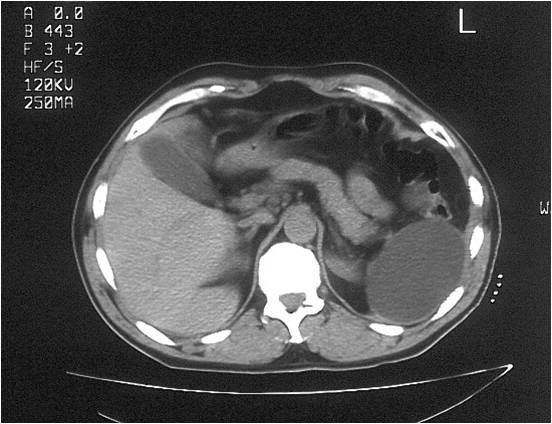

- Abscess post right hemicolectomy

- Successful placement and drainage